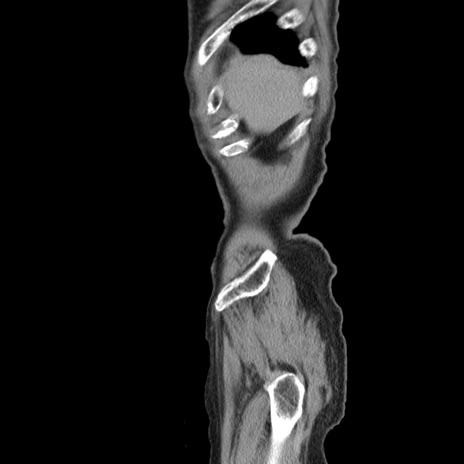

横断像